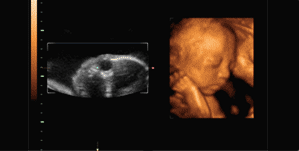

怀孕了就要做四维彩超,这是准妈妈们都知道的事儿!这不仅仅是因为四维彩超可以准确的为孕妈妈进行身体检查,而且比起普通B超和三维彩超,四维彩超可谓是孕期检查项目中最“靠谱”的了。具体怎么个靠谱法呢?下面我们就一起来了解一下吧!

四维彩超就是四维成像技术(4D),能直观,立体显示人体器官的三维结构及动态、实时地观察立体结构。主要可以进行龄检测、分析胎儿的发育情况、筛查胎儿畸形等。